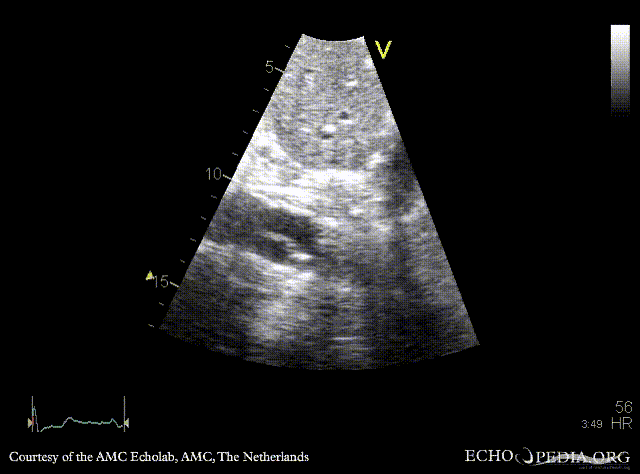

30 Aortic dissection

E00243.gif E00244.gif

PLAX: dilated aortic root and ascending aorta PLAX: Color Doppler, mild aortic regurgitation